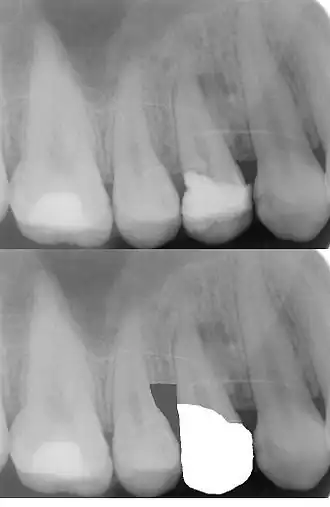

Ferrule-Effekt

Abgesehen von der Wiederherstellung eines ausreichenden Zahnfleischsaums trägt der Ferrule-Effekt zur Stabilität der künstlichen Zahnkrone bei.[6] Umfasst die zukünftige künstliche Zahnkrone den Zahn nicht bandförmig, steigt die Frakturgefahr eines wurzelbehandelten Zahnes.[6] In der oberen Röntgenaufnahme sieht man die an den Alveolarknochen angrenzende Zahnfüllung (weiß = röntgenopak). Auf der unteren Röntgenaufnahme sieht man die Kronenversorgung des Zahnes nach einer chirurgischen Kronenverlängerung im distalen Bereich, das heißt nach der Entfernung des Knochenseptums. (Die untere Röntgenaufnahme ist keine Originalaufnahme. Sie wurde digital bearbeitet, um das Prinzip der Kronenverlängerung aufzuzeigen).